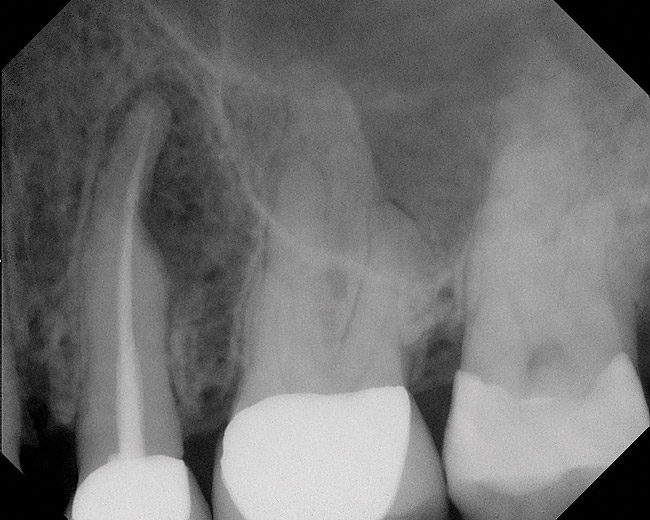

While not elaborated on here, it is noteworthy that there are a number of additional treatments for resorption that have been suggested in the literature, including calcitonin,27 Emdogain,24,28 and Alendronate (third-generation bisphosphonate in treating EIRR)29 (Figure 6, Figure 7, Figure 8, Figure 9, Figure 10, Figure 11, Figure 12, Figure 13, Figure 14 and Figure 15).

Cervical Inflammatory Resorption

Cervical inflammatory resorption (CIR) is a subclass of ERR. It is possible to have ERR below the epithelial attachment. In these clinical cases of CIR, the pulp is normal. Sulcular bacteria are suspected of providing the inflammatory stimuli that drive the process. Clinical management of this complex condition may be surgical, nonsurgical, or a combination of both modalities. It may also include orthodontic tooth movement or intentional replantation. It has been found that the treatment of cervical resorption is not as predictable if the process has progressed beyond the coronal third of the root.26

Teeth with CIR often have a questionable prognosis because of the periodontal and restorative needs that accompany this condition and the compromises that might occur to the long-term health of the periodontium as a result of the treatment. In addition, Class V restorations used to treat CIR are often traumatic to the pulp and lead to root canal therapy. Depending on the extent of the resorptive process, different treatment options have been proposed. Once perforation occurs then the success of retaining the tooth is dependent upon the severity of the defect. If the CIR is detected before perforation of the root, then conventional root canal therapy has a high rate of success. A crown-lengthening procedure can be considered if the area of resorption is not located too far subgingival (or subcrestal), which would affect the esthetics in addition to preventing restorative access. The long-term risk of vertical fracture, the time, costs, and numbers of procedures in addition to the long-term prognosis should be thoroughly reviewed before retaining these teeth. The patient should also be made aware of the long-term periodontal maintenance implications. If the clinician determines the tooth is nonrestorable then extraction with implant placement may be considered.